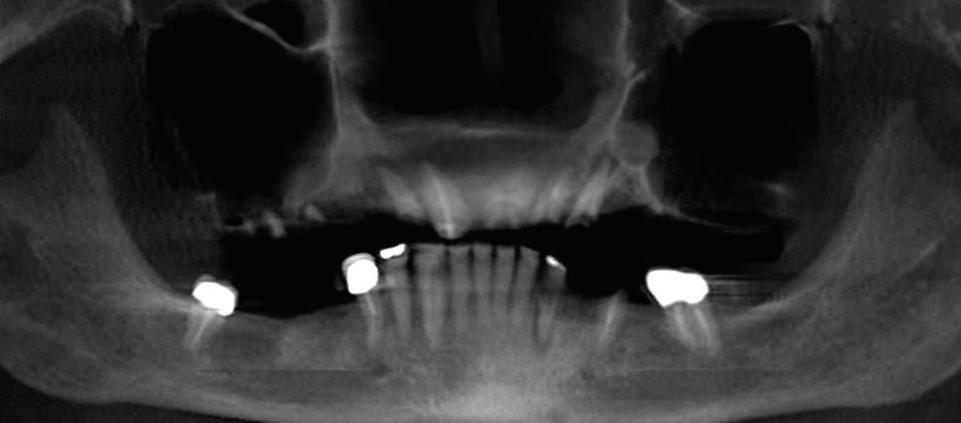

By E. Richard Hughes, DDS

Edentulous means lacking teeth. The complete loss of teeth (edentulism) due to gum disease and tooth decay can have severe consequences on your health. Complete dentures are an unacceptable substitute for natural teeth due to slippage, discomfort and inefficient chewing. Dental implants for endetulous patients are typically the best solution.

Edentulism is a complex condition due to the interaction between the disease and aspects that do not depend on the disease itself, such as biologic and patient factors. Edentulism presents socioeconomic problems to the worldwide health care systems.

Dental implant treatment can tremendously improve all the abovementioned issues.

Can just four implants replace all of the teeth on the top or the bottom of your mouth? Thanks to advances in dental implant technology, that answer is a resounding yes.

Believe it or not, tooth loss is extremely common among adults, especially as we age. In fact, more than 35 million people in America are missing all of their upper and/or lower teeth. Rather than living with the discomfort and hassles of dentures, many people are opting for what is called “all-onfour” dental implant restoration.

All-On-Four: One Full Arch Of Teeth, Four Dental Implants

To fully understand this remark-

able technique for replacing teeth, you should first understand what a dental implant is. An implant is a small titanium screw that fits inside your jawbone and replaces the root-part of a missing tooth. Minor surgery is required to insert the implants. Once the implant is in place, a crown is attached to give you a highly realistic-looking and functional prosthetic tooth.

Here’s where it gets really interesting: You do not need a dental implant for each and every one of your missing teeth. All you need is four precisely placed implants on the top of your mouth, and four on the bottom, to restore your full smile. That’s the beauty of the all-on-four. And because the implant is made of titanium, it has the unique ability to fuse to living bone and function as part of it. So eventually, the dental implant becomes part of the jawbone and serves as a strong, long-lasting foundation for your new teeth.

Besides ensuring that your implants are permanently fixed in place,

this bone fusion has another important benefit: it prevents future bone loss in the jaw. This helps to maintain a more youthful facial structure – and better oral health. But perhaps the biggest surprise about the all-on-four is how quickly it can transform your life.

What’s The All-On-Four Dental Implant Procedure Like?

It can be scary to get implants for the first time. Most of that fear is probably due to the uncertainty, so here is the step-by-step process for getting an All-On-Four dental implant.

First, your dentist will want to make sure your comfortable, so either local or general anesthesia will be administered.

Second, the dentist or surgeon will prepare your mouth for the implants, which involves removing your remaining teeth that are failing. They will then remove any diseased or infected tissue from your jaw and gums.

Next, they will begin the implantation process. This means they will

insert the titanium screws into your jawbone. Most likely, they will place two implants toward the front of your mouth and two towards the back of your mouth so the “anchors” can evenly bare the force of the denture.

After the implants have been placed, they will thoroughly clean the surgical sites and suturing all the incisions. Then you’ll be taken to a recovery room where you can relax and take time to wake up from the anesthesia.

How Do You Know If The All-On-Four Procedure Is The Right Option For You?

At your All-On-Four consultation, you’ll receive a 3D CT Scan. This scan will help determine if you need implants and assist your doctors in creating your treatment plan. So if you want to learn more about dental implants, simply schedule a consultation with an All-On-Four provider. It’s the best way to find out how dental implants can change your life.